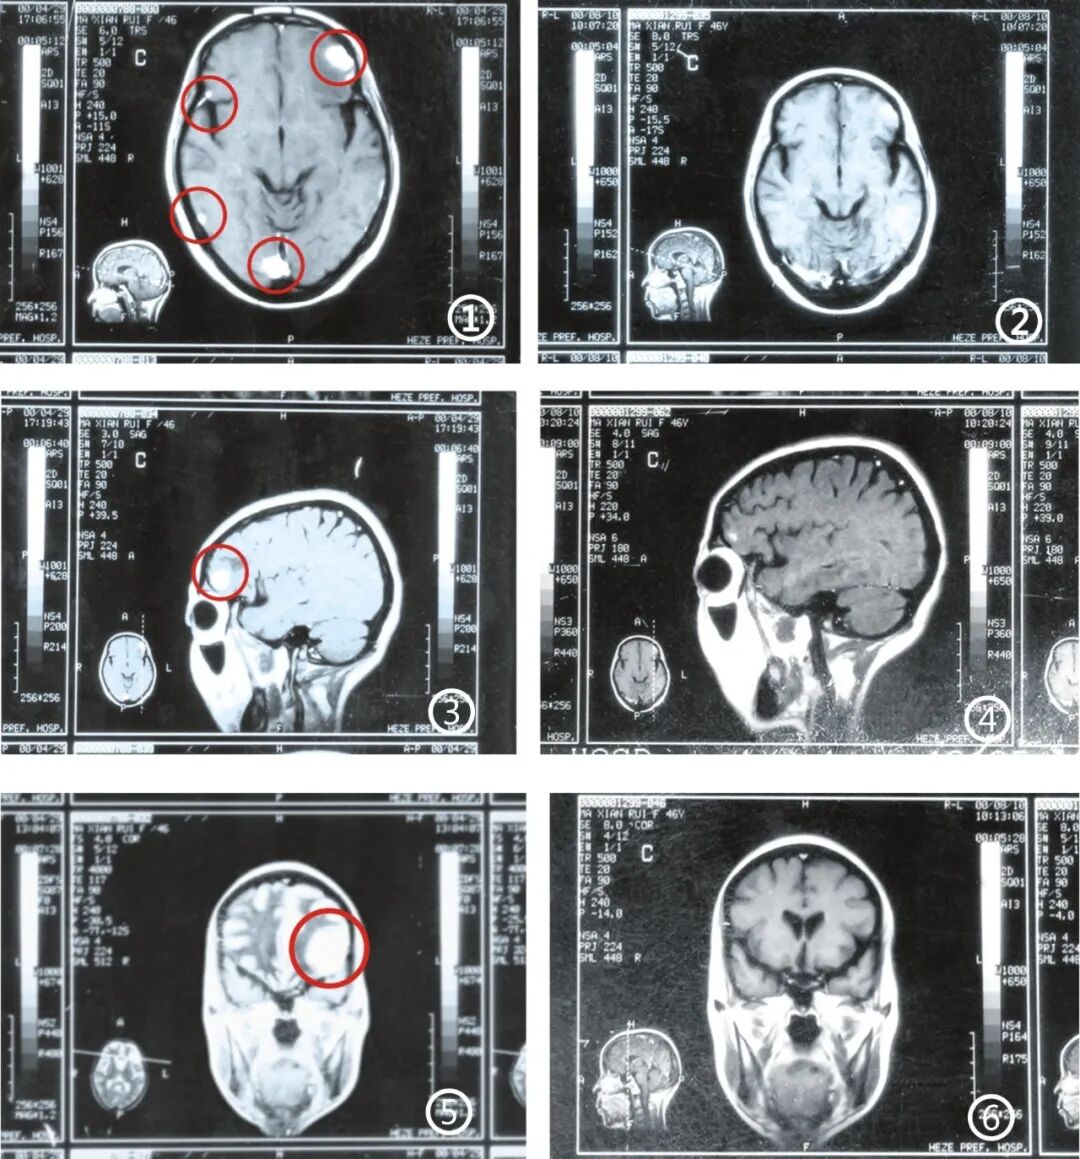

“脑转移瘤,是什么?”

“转移了,啥意思?”老伴说,那是2000年5月,给房子边扫地嘞,邻居过来给我,“快去看看,马先蕊给门口台阶摔倒了”。当时发病特别“急”,一倒下几天就不会走了,带着在菏泽拍了3次磁共振,查不出来,到济南省立医院,才被鉴定为:“脑转移瘤”。

那是26年前,不懂呀,哪知道啥意思呀!一问就是“恶性肿瘤”。有什么办法吗?“没有,不能手术”。那一刻,天都要塌了。但看着病床上的妻子和三个懵懂的孩子,丈夫马心如硬是把绝望咽进了肚子里。他放下了手头正红火的生意,独自一人在菏泽、济宁、济南的大医院之间奔波。可跑断了腿,听到的都是摇头。有医生建议试试伽马刀(放疗),但也只能无奈地补一句:“不敢保证有效。”

可是没办法了,总要试试。丈夫马心如记得:“脑上瘤子密密麻麻,有3个大块,像黄豆一样大”,想试伽马刀,一个块1万,先交3万。

眼见为实,丈夫赶紧带妻子马先蕊去做了个磁共振。拿着片子对比一个月前的老片,医生都惊呆了:“病情控制住了,没发展!你们怎么治的?”喝了中药,医生连连称奇:“这真是个奇迹!这药不能停,等好了记得把情况反馈给我,我要把这个病例记下来!”

为了确认肿瘤到底消没消,丈夫又带妻子做了增强CT。检查医生看着片子,语气里满是惊喜:“比二十多天前又缩小了!这药管用,千万别乱停!”

就这样坚持着,原来米粒大的肿块不见了,黄豆大的另外2个瘤子也缩成了黑影,最后彻底消失。

“后来问的人实在太多了,瞒也瞒不住,索性就告诉她实情了。”为了让妻子彻底放心,他们又去复查了一次。医生指着片子说:“脑部一切正常,原来的黑点都没了,放心吧!”